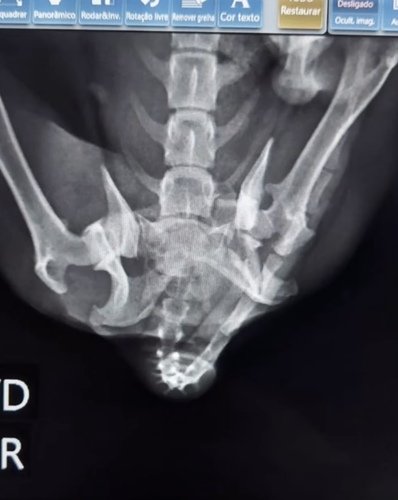

Oi, pessoal! Estamos aqui para pedir a sua ajuda para a nossa querida Malu, uma cachorrinha resgatada cheia de amor e alegria, que infelizmente foi atropelada e agora não consegue mais andar.

Ela precisa passar por uma cirurgia urgente para ter a chance de recuperar seus movimentos e voltar a correr e brincar como antes. O custo do procedimento é alto, e não conseguimos arcar com todas as despesas sozinhos.